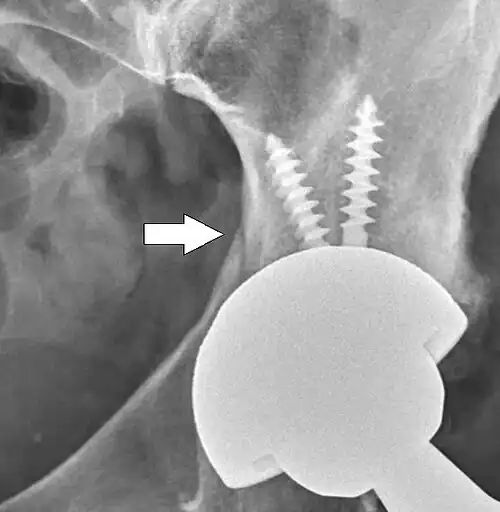

Hemiarthroplasty

Hemiarthroplasty is a surgical procedure that replaces one half of the joint with an artificial surface and leaves the other part unchanged. This class of procedure is most commonly performed on the hip after an intracapsular fracture of the femur neck (hip fracture). The procedure is performed by removing the head of the femur and replacing it with a metal or composite prosthesis. The most commonly used prosthesis designs are the Austin Moore and Thompson prostheses. A composite of metal and high-density polyethylene that forms two interphases (bipolar prosthesis) can be used. The monopolar prosthesis has not been shown to offer any advantage over bipolar designs. The procedure is recommended only for elderly/frail patients, due to their lower life expectancy and activity level. This is because over time the prosthesis tends to loosen or to erode the acetabulum.[101] Independently mobile older adults with hip fractures may benefit from a total hip replacement instead of hemiarthroplasty.[102]

Hip prosthesis for hemiarthroplasty. This example is bipolar, meaning that the head has two separate articulations. -

X-ray of the hips, with a right-sided hemiarthroplasty